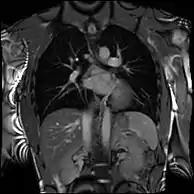

همراه با استرس وازودیلاتور (اتساع عروق)، در تشخیص و توصیف ایسکمی میوکارد (بیماری شریان کرونی) به دلیل بیماری در عروق اپیکارد و ریزجریان نقش دارد. تقویت گادولینیوم دیررس (LGE) و نقشهبرداری T1 به سکته قلبی و فیبروز (فساد الیاف) برای تشخیص کاردیومیوپاتی و ارزیابی قابلیت زنده ماندن اجازه میدهد.[7] آنژیوگرافی تشدید مغناطیسی ممکن است با تقابل یا بدون تقابل انجام شود و برای ارزیابی ناهنجاریهای مادر زادی یا اکتسابی عروق کرونر و عروق بزرگ استفاده میشود.[8]

جریان چهار بعدی CMR

تصویربرداری کنتراست فاز معمولی را میتوان با استفاده از شیب حساس به جریان در ۳ طرح متعامد در یک حجم سه بعدی در طول چرخه قلب افزایش داد. چنین تصویربرداری چهاربعدی، سرعت جریان خون در هر وکسل را در کد رمزگذاری میکند و باعث میشود دینامیک سیال با استفاده از نرمافزارهای ویژه قابل مشاهده باشد. برنامههای کاربردی در بیماری پیچیده مادرزادی قلب و برای تحقیق در مورد ویژگیهای جریان قلب و عروق وجود دارد - اما به دلیل پیچیدگی مراحل پس از پردازش و زمان کسب نسبتاً طولانی در استفاده روتین بالینی نیست.[23]

جریان داخل و خارج از قلب در یک حجم چهار بعدی با زمان حل شده شامل قلب و عروق بزرگ مشاهده میشود.

سمت چپ: سرعت جریان. مرکز: خطوط جریان. سمت راست: بردارهای جریان.کودکان و نقض مادرزادی قلب